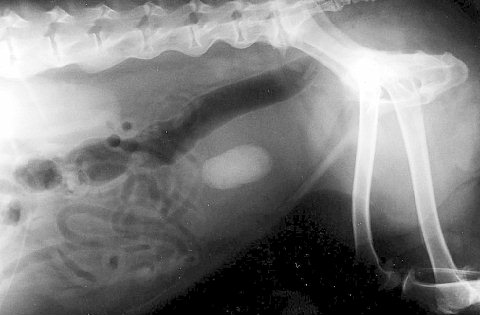

次は水腎症と言って、腎臓の周りに水(尿)が溜まってしまう病気です。

こうなってしまうと腎臓は元の形を留めていませんし、機能は完全に破綻しています。

幸いもう片側の腎臓は正常でしたので、悪い方は切除しました。

そしてこれが摘出した腎臓です。